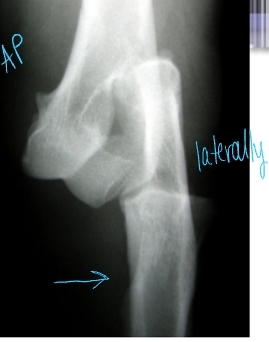

Elbow Luxation

Et: Traumatic most common

Traumatic: Radius and ulna luxate laterally

large medial condyle of humerus prevents medial luxation

Congenital: abnormally shaped radius/ulna/ humerus

Cs: Unable to bear weight, Forelimb abducted and externally rotated (elbow out, paw rotated in)

Dt: limb resists extension, prominent radial head, PAINFUL, Radiographs AP views!

Tx:

Acquired: Closed reduction under GA + brachial plexus block

Flex elbow to 100° and internally rotate

Extend elbow slightly, adduct and inwardly rotate antebrachium while applying medial pressure on radial head

Immobilize 2 weeks w/ spica split

Congenital

If reducible → place transarticular pin while still growing!! remove later on

If non-reducible → arthrodesis when older in standing position